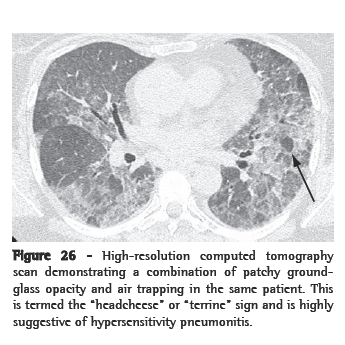

In a normal host who is a nonsmoker and does not have cardiac failure, the most common cause of ground-glass opacity is HP.(84) In HP, ground-glass opacity indicates subacute disease. With relevant exposure, a ground-glass opacity pattern associated with centrilobular nodules and lobular air trapping (the so called "head-cheese pattern" or "terrine sign", Figure 18) is highly suggestive of the diagnosis.

"Headcheese" or "terrine" sign

The combination of ground-glass opacity and mosaic perfusion in the same patient is termed the "headcheese" or "terrine" sign (Chart 13; Figures 26 and 27). This gives the lung a heterogeneous appearance with three lung densities: high attenuation (ground-glass opacity); normal; and low attenuation (mosaic perfusion). Since it is typically due to HP, this is a quite useful finding.(136)